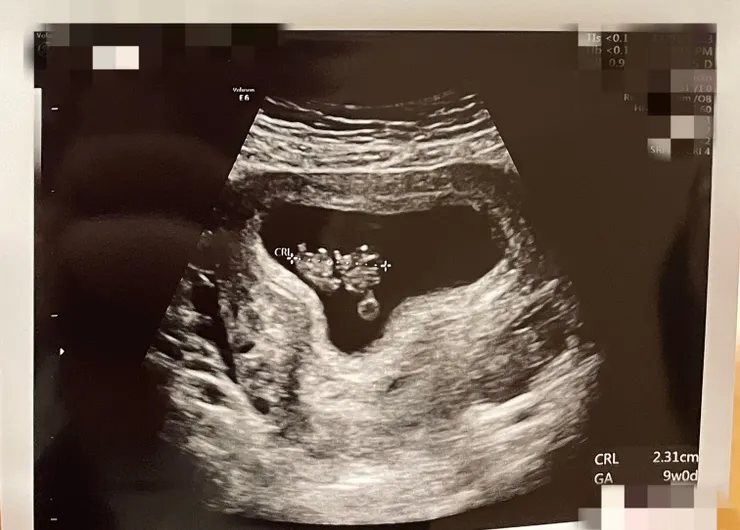

第八週(8w+4)去看婦產科

這次可以從肚皮照超音波觀察

再一次校正胎兒大小和預產期

這次檢查校準足足多加了四天

可說是直接就進入第九週孕期

超音波照到的胎兒還自帶餐盒

卵黃囊清楚可見提供初期營養

最底部小圓圓處是便當盒啊:)